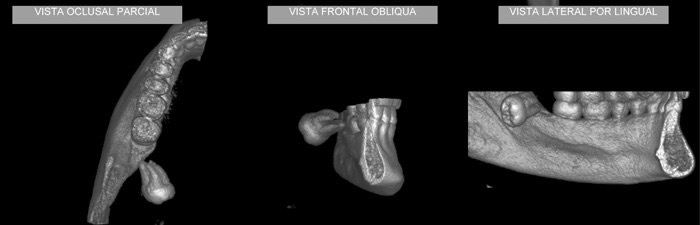

Caso 1: Anquilose de ATM

Paciente com assimetria, limitação de abertura bucal. Observa-se união óssea da porção posterior e lateral do côndilo ao esfeóide e zigomático.

Caso2: Localização de dente retido

História clínica de exodontia do dente 38 há um ano, sem no entanto localizar o elemento dentário acreditando que o paciente havia engolido o dente. Na radiografia panorâmica observa-se a presença do dente 38 superposto ao ramo. Na tomografia localiza-se o dente no assoalho bucal.